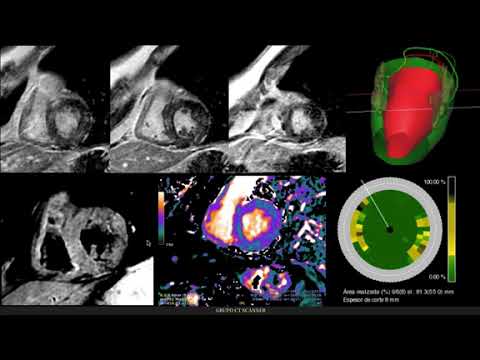

Diagnóstico precoz de la cardiotoxicidad de la quimioterapia

Dra. Zuilma Vazquez

Aporte de las imágenes en el estudio de la hipertrofia ventricular

Dr. Sergio Baratta

Técnicas Avanzadas de Cardio RM: protocolos y aplicaciones clínicas

Dr. José Gutierrez